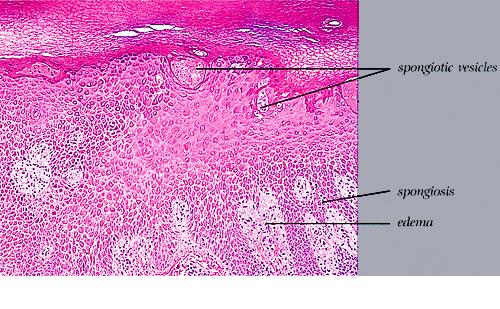

Histopathology. Spongiosis and intraepidermal vesiculation occur in acute lesions . There is a superficial perivascular Iymphohistiocytic infiltrate with exocytosis of lymphocytes into spongiotic zones. The infiltration is usually mild. In acute lesions, the compact, thickened stratum corneum of acral skin remains intact, and the epidermal thickness is normal. With chronicity, spongiosis diminishes; acanthosis and parakeratosis predominate with variable crusting. Difficulty in differential diagnosis with pustular psoriasis may occur because of the formation of vesiculopustules in older lesions. A periodic acid-Schiff (PAS) stain should always be performed on vesicular lesions of the palms and soles, because tinea manus/pedis may mimic dyshidrotic dermatitis histologically. |